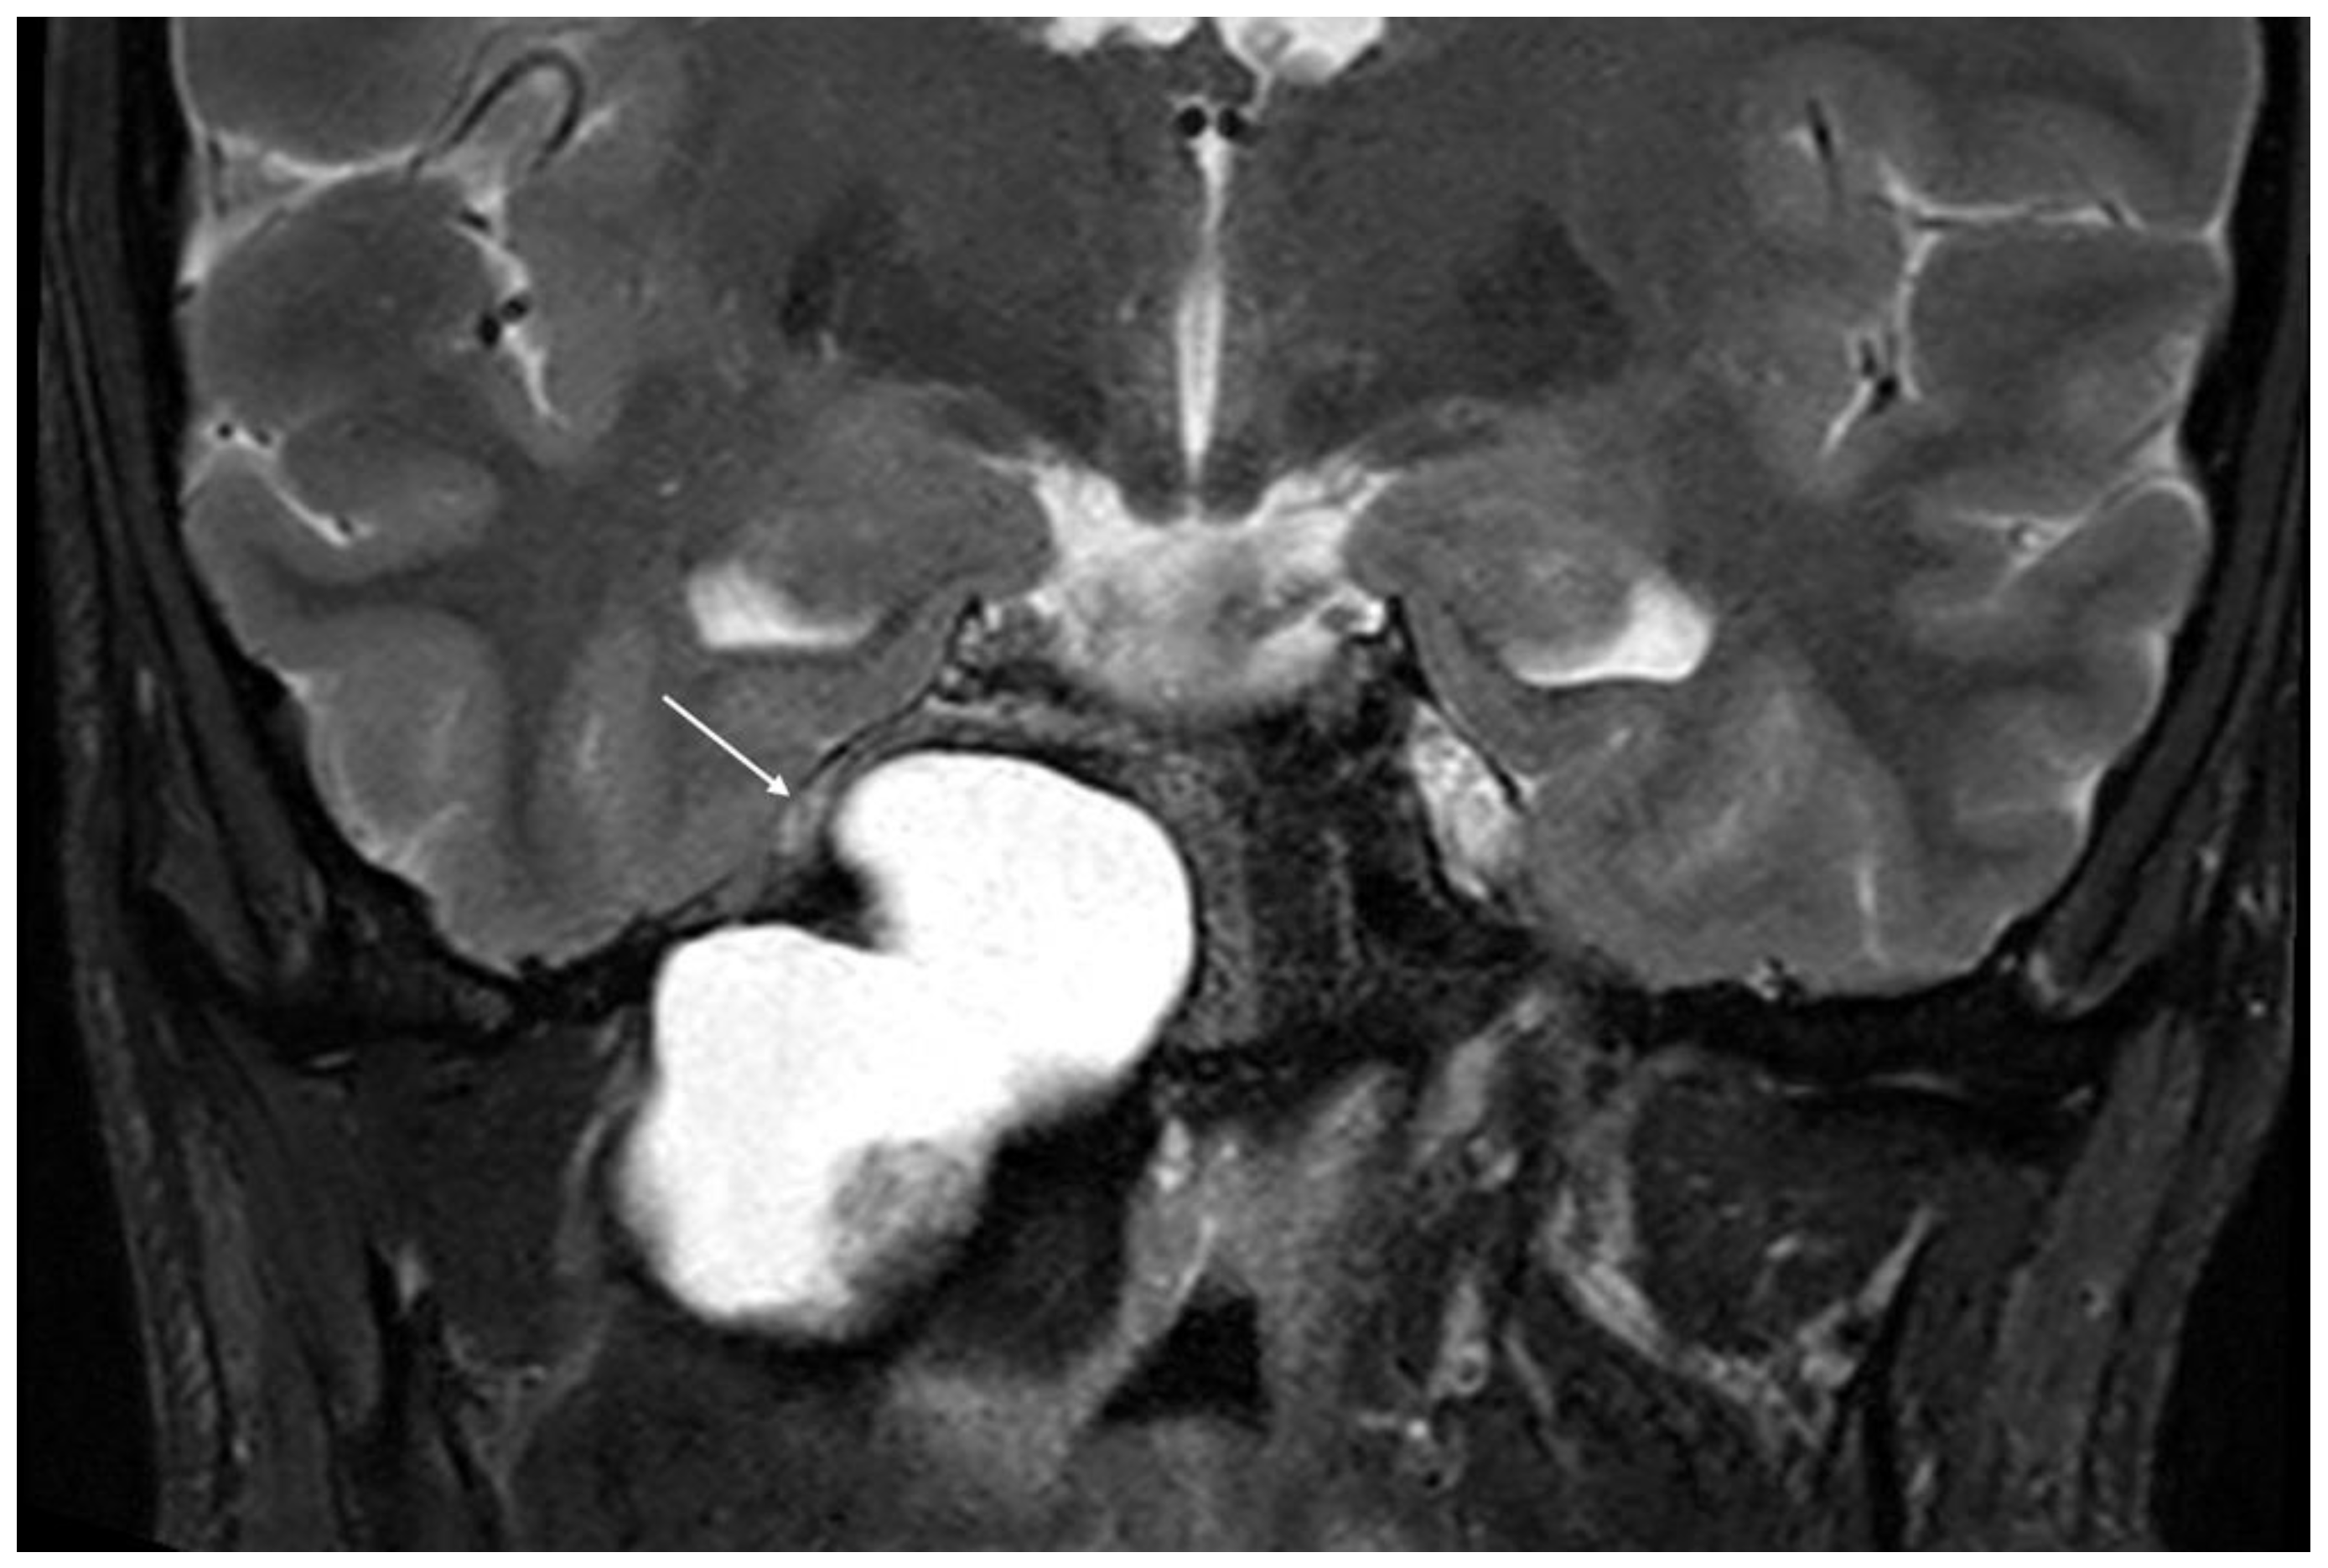

Imaging data from each patient were examined by an expert radiologist and an ENT specialist focusing attention not only on the location of the cyst, but also on the adjacent structures involved. Considering the available literature on symptoms and hypothesized regions of radiological involvement, we established a reproduceable pre-operative radiologic map to better correlate typical symptoms, such as headache, hearing loss, vestibular symptoms, tinnitus, otitis media, diplopia, and facial paresthesia, with PACG. The following regions were considered: (1) temporal lobe/posterior fossa compression (Figure 1); (2) Meckel’s cave compression (Figure 1); (3) Eustachian tube compression/erosion (Figure 2); (4) internal auditory canal erosion (Figure 3); (5) cochlear basal turn erosion (Figure 4); (6) Dorello canal involvement (Figure 5); (7) jugular tubercle erosion. The latter parameter was introduced to evaluate its possible correlation with an atypical clinical presentation, namely fainting. To standardize all these radiological examinations, the jugular tubercle was defined in axial sections as the bony convexity medial to the jugular foramen just above the hypoglossal canal; in coronal sections, it is the bony part directly above the hypoglossal canal (Figure 6).

Figure 1. Coronal T2-weighted MRI demonstrating compression of the temporal lobe and Meckel’s cave region (white arrow) by cholesterol granuloma of the petrous apex.